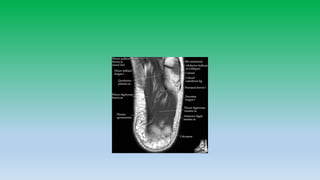

10. Mid-sagittal T1 WI shows the small os trigonum Corresponding sagittal IR image shows bone marrow edema in os trigonum (arrow); as well as in adjacent talus head (arrowhead).